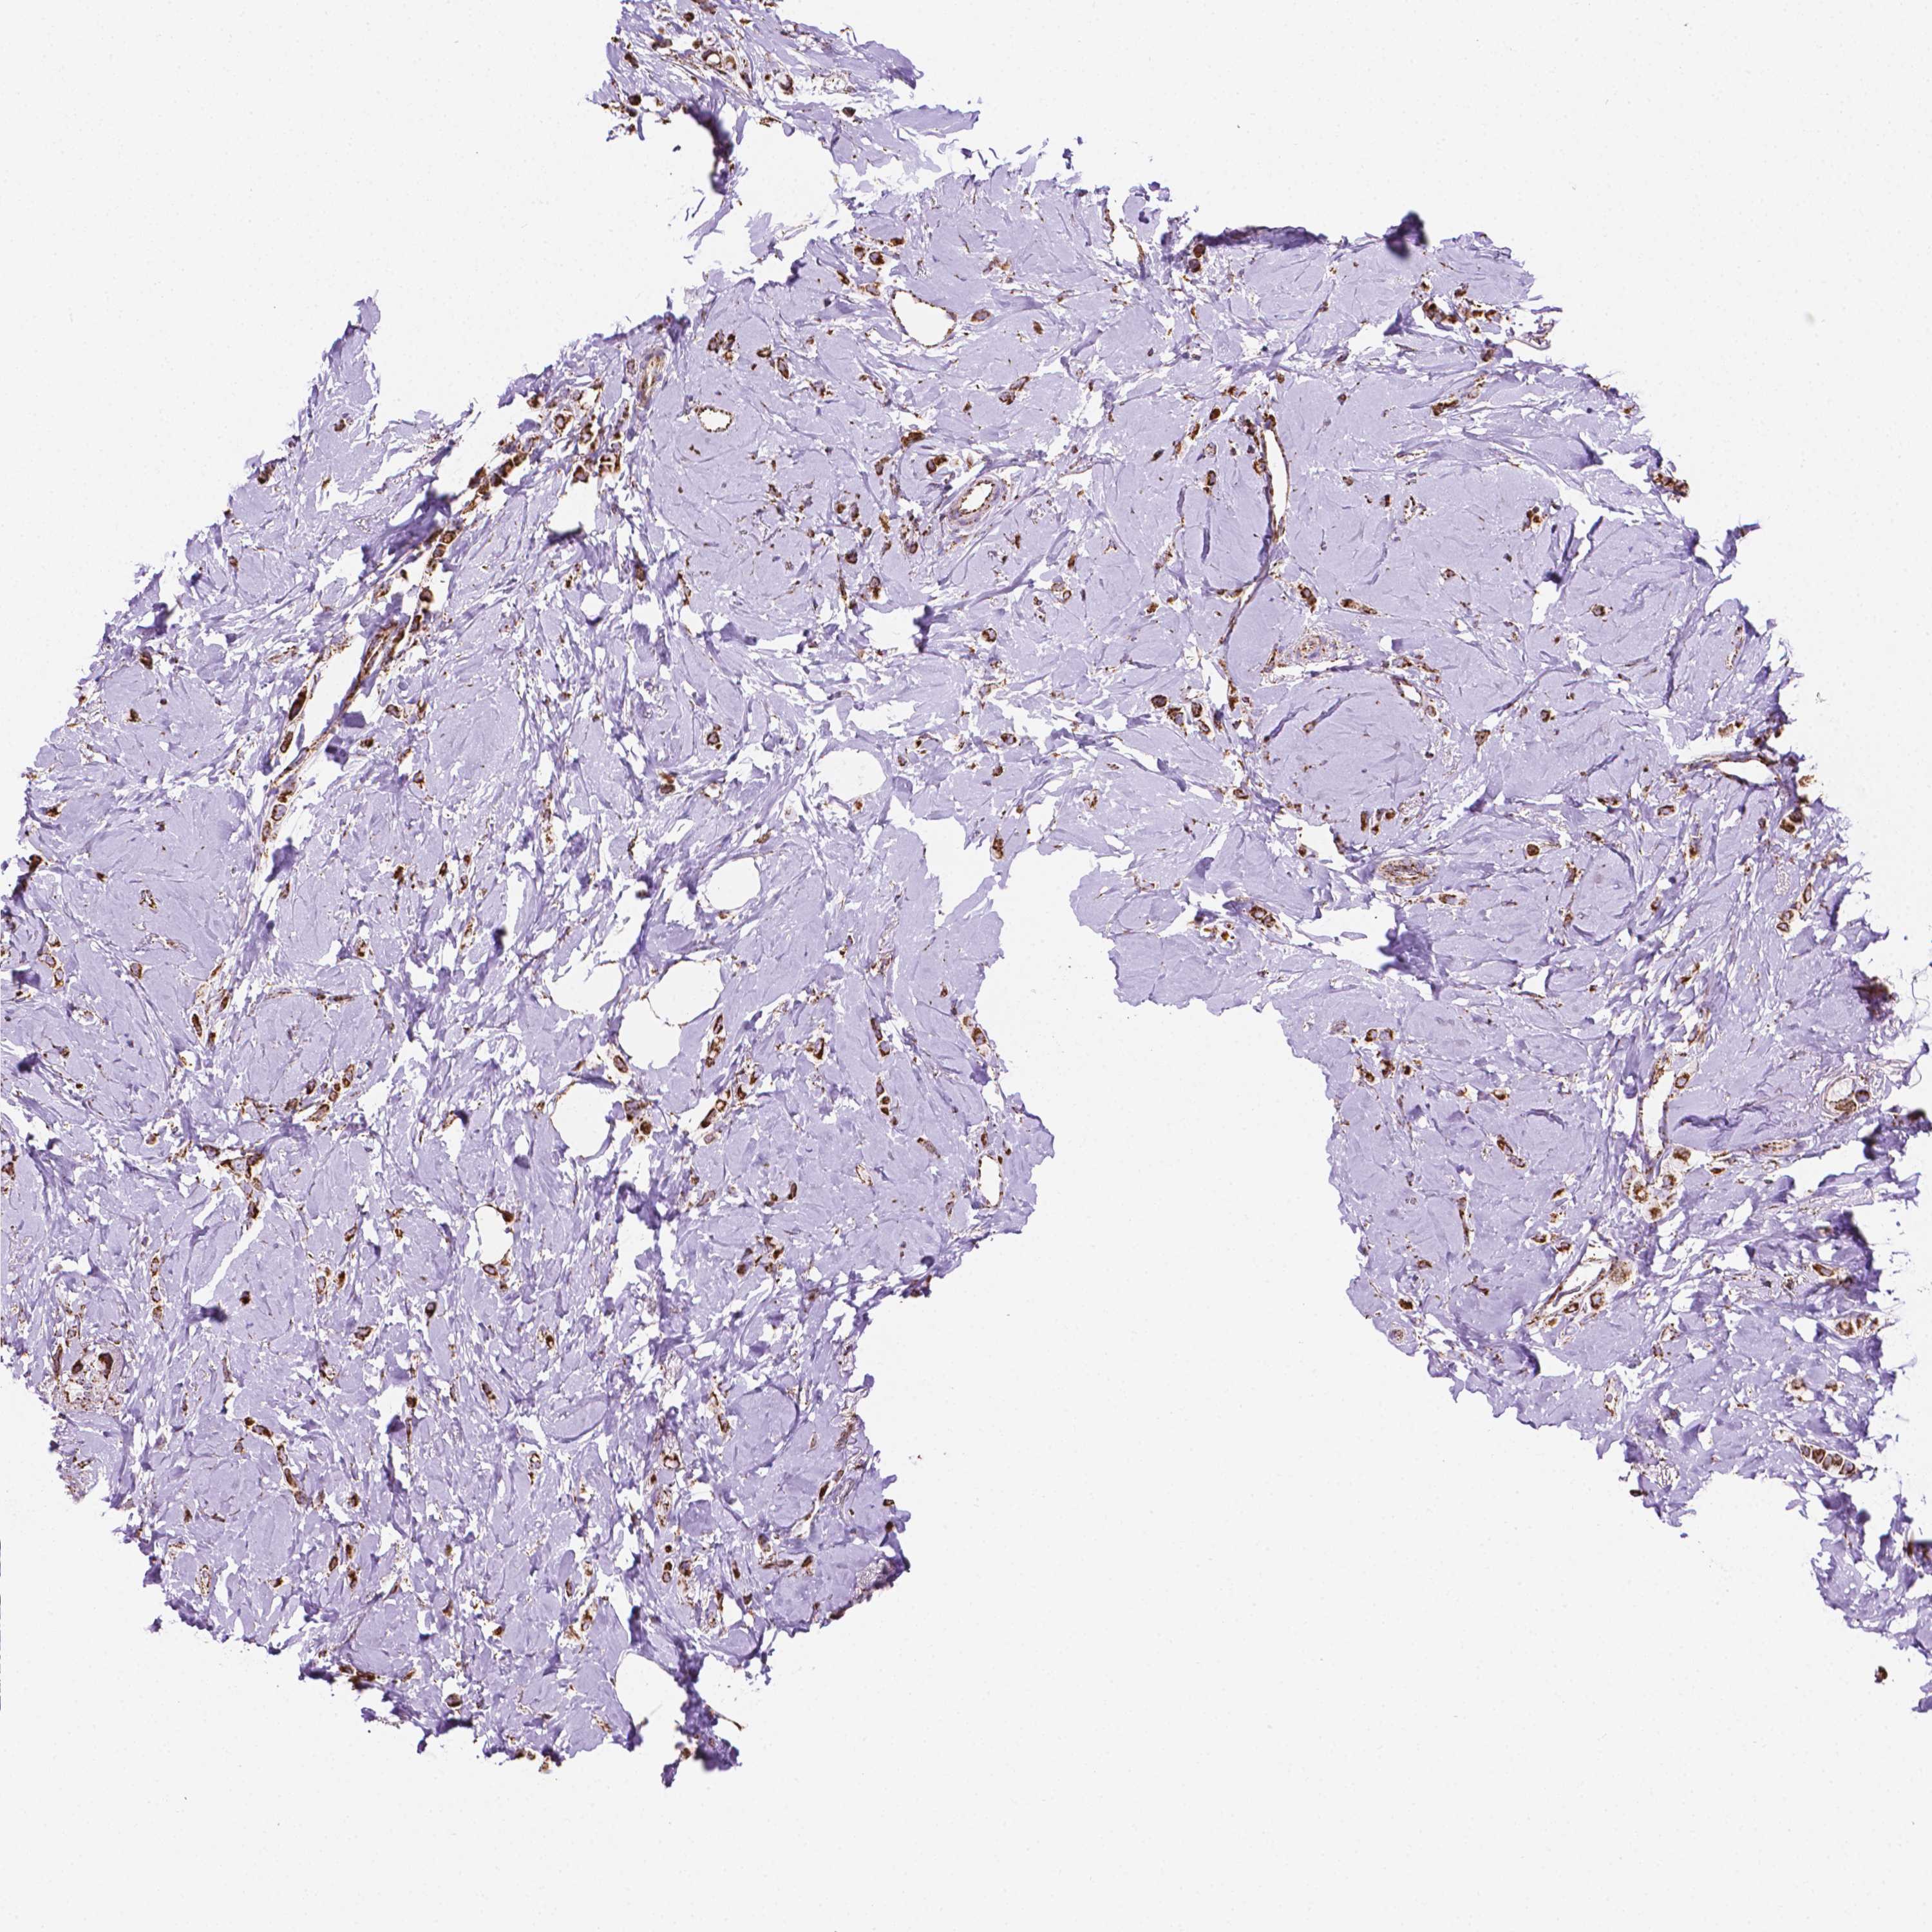

BRCA TCGA BRCA VALIDATION PROTEIN EXPRESSION

ANTIBODIES

AND

VALIDATION